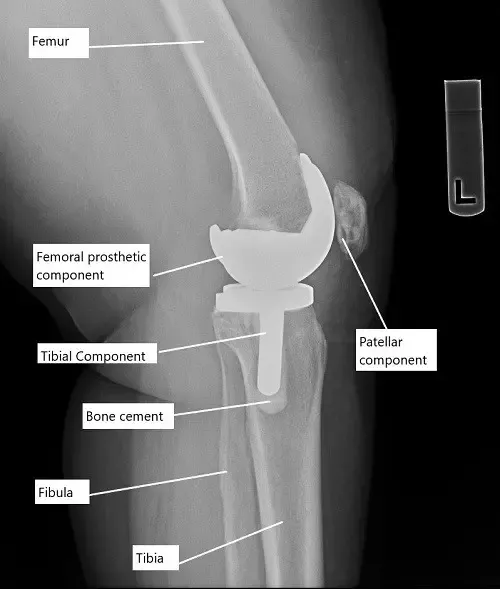

X-ray showing total knee replacement.